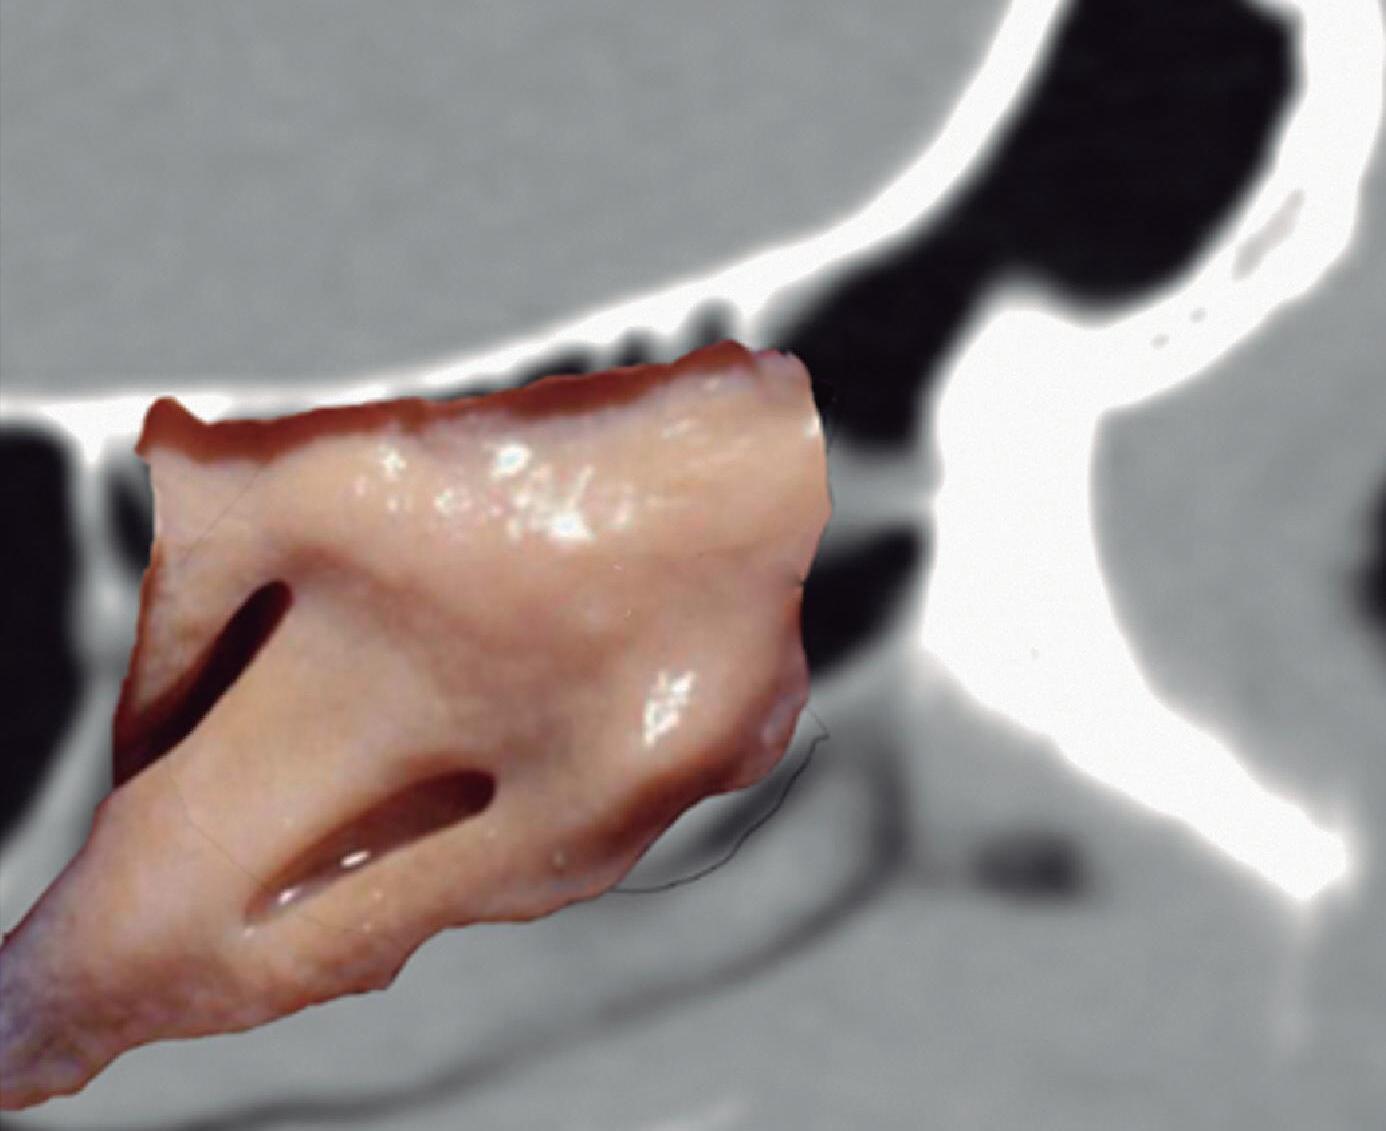

Utilizamos muitas vezes o programa “Nasal Vista”, desenvolvido na Espanha por meu ex-fellow Guillermo San Juan e pelo autor, programa este construído após digitalização de 600 tomografias computadorizadas e que oferece imagens anatômicas detalhadas juntamente com o estudo radiológico, tornando-se uma ferramenta didática muito útil.

1-4. TC e reconstrução 3D com destaque para estrutura etmoidal (em vermelho), funcionando como câmaras de baixa pressão para drenagem do seio maxilar.

1-7. TC com reconstrução 3D mostrando em vermelho apenas o seio etmoidal e não o osso etmoidal, e sua relação com a fossa nasal, o seio maxilar, órbita e fossa anterior.

1-8. Osso etmoidal e seio etmoidal (amarelo) observar o aspecto incompleto do teto do seio etmoidal que será coberto pelo osso frontal (rosa).